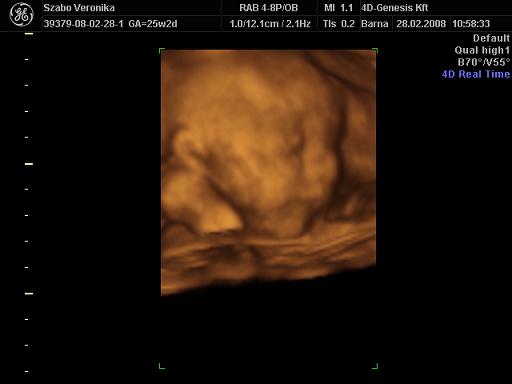

Én is szeretnék látni képeket!

Akik a baba méretei miatt aggódnak, elmondanám, akárhogy is lesz, akármekkora is lesz,:

ODABENN NEM MARAD!!!!!

Emlékszem, engem a második szülésem alatt csak ez vígasztalt...